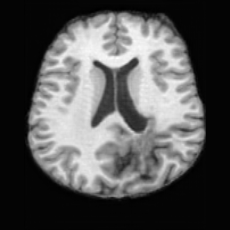

(a)PathologicalInput ImageSynthSR [18]Brain-ID [28]UNA [30]USBHealthyGround TruthRefer to captionRefer to captionRefer to captionRefer to captionRefer to captionRefer to captionRefer to captionRefer to captionRefer to captionRefer to captionRefer to captionRefer to captionRefer to captionRefer to captionRefer to captionRefer to captionRefer to captionRefer to captionRefer to captionRefer to captionRefer to captionRefer to captionRefer to captionRefer to caption(b)HealthyInput ImageConditionalLesion MaskUNA [30]USBRefer to captionRefer to captionRefer to captionRefer to captionRefer to captionRefer to captionRefer to captionRefer to captionRefer to captionRefer to captionRefer to captionRefer to captionRefer to captionRefer to captionRefer to captionRefer to caption

Figure 5: Comparison of bidirectional brain editing. (a) pathology-to-healthy, the circles and arrows highlight lesion regions and unsuccessful reconstructions; (b) healthy-to-pathology. Note that SynthSR and Brain-ID cannot perform healthy-to-pathology editing.

Pathology-to-Healthy Editing. Fig. 5 (a) presents comparison results on four input brain images with lesions of varying sizes, shapes, and densities. All competing models, although specialized for healthy brain image synthesis, struggle to reconstruct pathological regions, especially near lesion boundaries. In contrast, USB accurately reconstructs the corresponding healthy brain, even in challenging cases with large, high-density lesions where normal brain structures are almost completely obscured (last row). Tab. 2 provides a quantitative comparison for pathology-to-healthy editing, where USB achieves the best performance across all three datasets, demonstrating the effectiveness of its unified framework in reconstructing healthy brains from pathological inputs. Additional results are in Suppl. B.